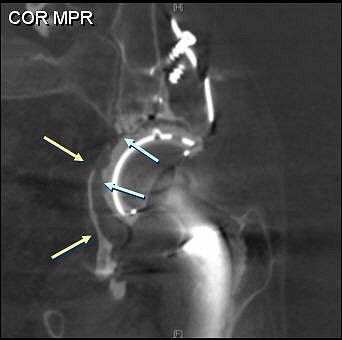

![]() |

| A 61-year-old woman with bilateral hip prostheses who was referred before surgery for evaluation of remaining "bone stock" surrounding cetabular hardware. Multislice CT was performed with thin slices (2.5-mm slice width, 1.4-mm reconstruction interval), high kilovoltage (140 kVp), and high tube current (750 mAs). Coronal reformatted image shows sparse amount of bone surrounding acetabular components (solid arrows). Wear of plastic joint liner of right hip (open arrow) is shown. Optimal scanning technique minimized metal artifacts. Buckwalter KA, Rydberg J, Kopecky KK, Crow K, Edward L, Yang EL, "Musculoskeletal Imaging with Multislice CT" (American Journal of Roentgenology, 2001; 176:979-986). |